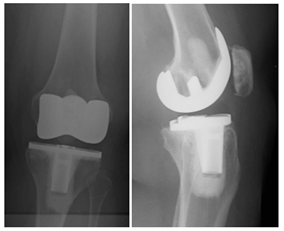

She did well for a year and a half following her revision surgery then presented with knee pain located medially on the joint line, over the pes bursae as well as along her distal IT-band. It was also noted in flexion that her excess soft tissue from her posterior thigh impinged on her posterior leg. Radiographs were obtained (Figure 3), and revision surgery to a hinge type knee was recommended to control AP instability, particularly given the posterior impingement of her soft tissues in the popliteal region secondary to her body mass distribution, which on exam appeared to be causing anterior tibia translation and likely contributing to the catastrophic posterior medial tibia failure.

The patient waited, given her symptoms at this time frame were only mild; however, 4 months later she presented for follow up, as she was having significant instability (Figure 4). She was then scheduled for revision TKA.

Figure 3 AP/Lateral left knee, 16months following revision surgery, again demonstrating anterior tibia translation and joint line asymmetry concerning for mechanical failure of the polyethylene.

Figure 4 AP/Lateral left knee 20months from revision surgery demonstrating increased anterior tibia subluxation and medial joint space narrowing. There is also evidence of posterior medial tibia tray fracture.